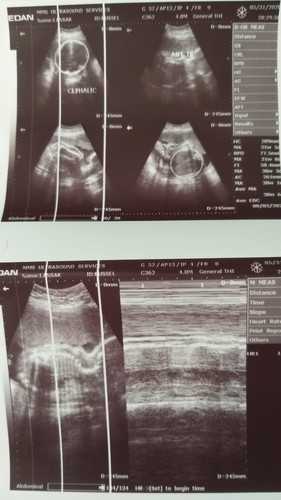

Hello po mga momshie... Ask ko lng po sn po makikita ung gender ni baby sa ultrasound na to? Sabi po kc sken baby BOY dw po ... Thank you po sa mkakapansin First time mommy

Yung may binilogan po